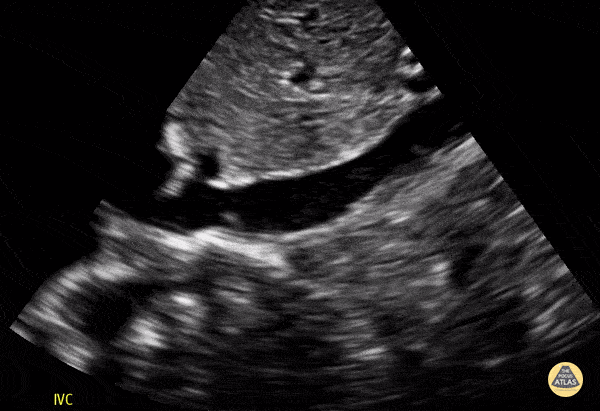

Normal IVC in a 9-year-old. Contributor: Jaron Smith, MD, Phoenix Children's Hospital

View: Unspecified Parasternal Long Axis Parasternal Short Axis Apical Four-Chamber Subcostal Four-Chamber Subcostal Inferior Vena Cava Right Upper Quadrant Left Upper Quadrant Suprapubic Longitudinal Suprapubic Transverse Subxiphoid Anterior Thoracic Phrenic